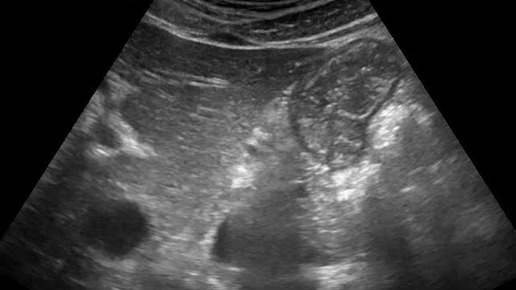

Видео к статье "Ультразвуковая визуализация складок слизистой оболочки желудка"https://dzen.ru/a/Zxn0nKmmrxNWvz-b